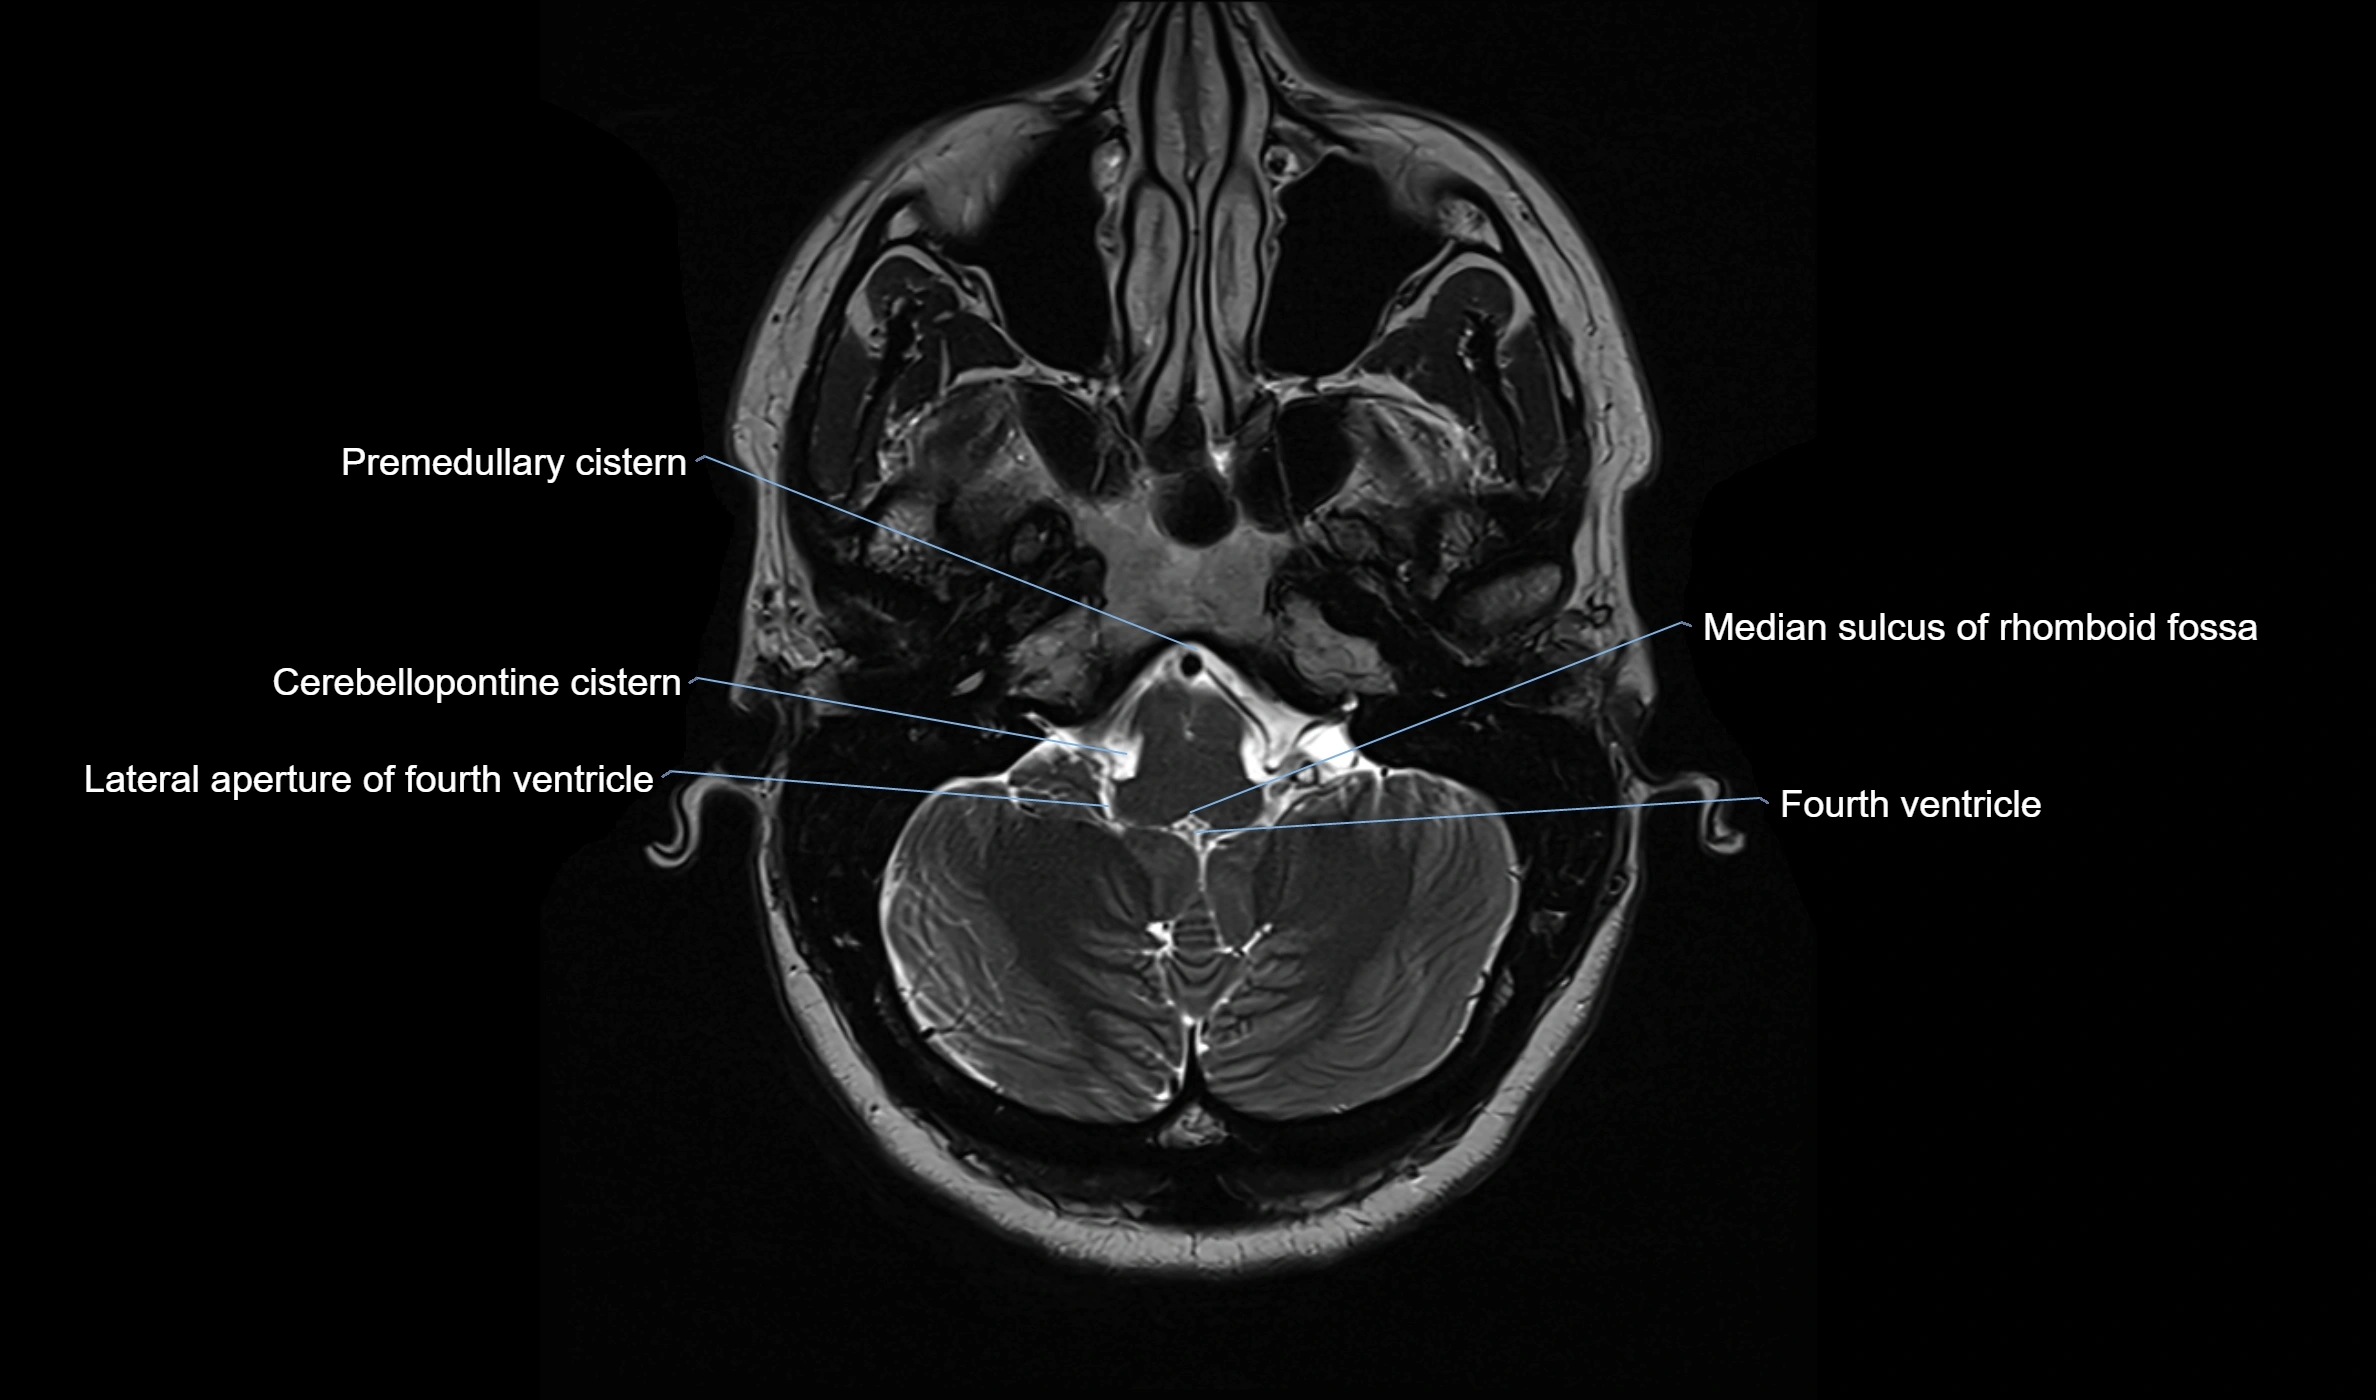

MRI images

image